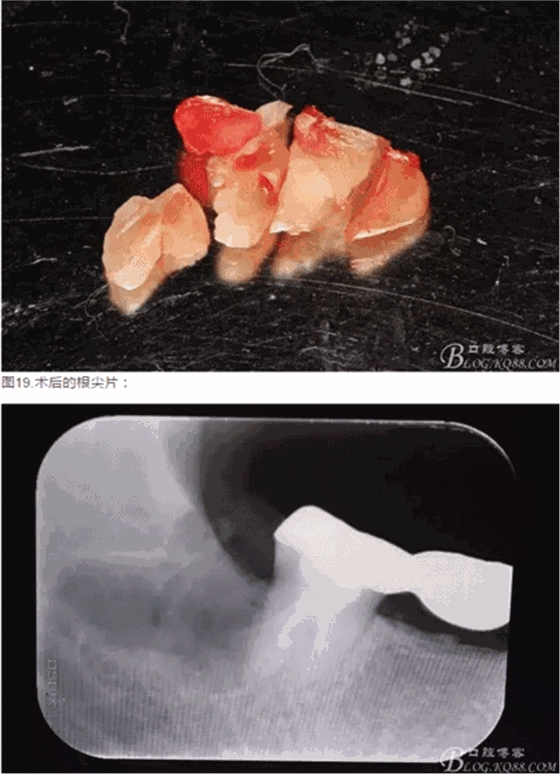

圖18.大卸八塊的牙齒,之所以分這么多塊,就是為了取這些牙體組織的時候不會碰到前面的47全瓷冠。

圖15。為了減少去骨,又把牙根橫分成兩塊取出來,這是拔完牙后的牙槽窩情況,我提倡小切口、翻小瓣、少去骨、多分牙原則。目的是為了減輕術(shù)后反應(yīng)。